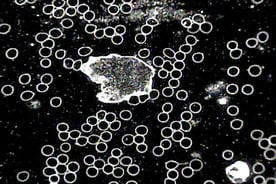

Darkfield microscopy (also known as Live Cell Analysis/Microscopy) is a simple and useful technique of analyzing blood from a patient for information about the terrain (i.e. acid/base balance), the immune system, nutritional status, and the state of various microorganisms.  A darkfield microscope produces an image with a dark background and looks at live, unstained, and unfixed blood, unlike the conventional light field microscopy or electron microscope.  Without stains and fixatives, the picture reveals a continuum rather than a moment in time.  It allows the ability to view blood in its mobile nature (i.e. red blood cells and white blood cells floating in the plasma), and even microbial (bacterial and fungal) activity and their different forms.

Professor Gunther Enderlein, a German zoologist and physician, discovered several fundamental concepts in understanding the nature and biological cause of disease.  These concepts include:   the “Pleomorphic Theory,” which states that each microorganism (bacteria and fungus) undergoes a life cycle where one can see changes in shape and behaviour; the fungal element protit, not the cell, is the smallest biological unit in human blood; the existence of two microorganisms within the blood of all mammals:  Mucor racemosus Fresen and Aspergillus niger Van Theigen; within the blood, these microorganisms can change form depending on the individual’s body terrain or environment, and can ultimately affect the body’s normal processes to promote a variety of diseases.